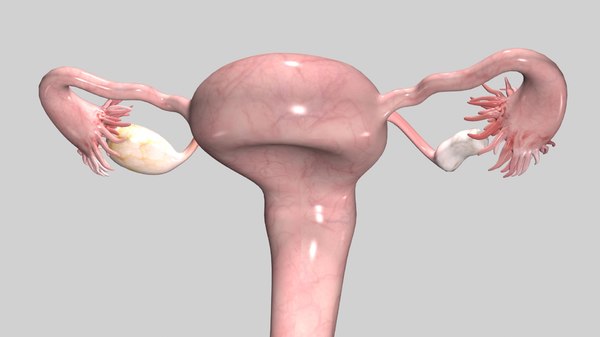

Анатомия женского организма: строение и функции матки